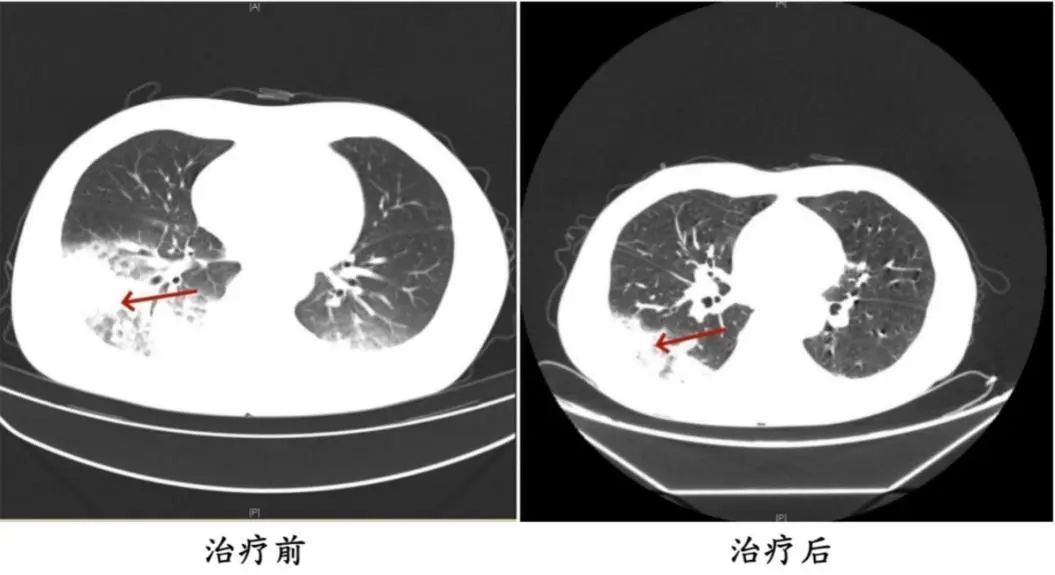

周先生治疗前后的肺部CT影像

医生判断患者有可能感染了军团菌,建议患者完善纤支镜检查,留取肺泡灌洗液标本查找病原体。最终,患者肺泡灌洗液NGS(Next-Generation Sequencing,下一代测序)检测结果显示:嗜肺军团菌,明确诊断为军团菌肺炎。医生马上调整治疗方案,改用可覆盖嗜肺军团菌的一线用药抗感染,患者体温逐渐下降,次日体温恢复正常,经过后续治疗康复出院。